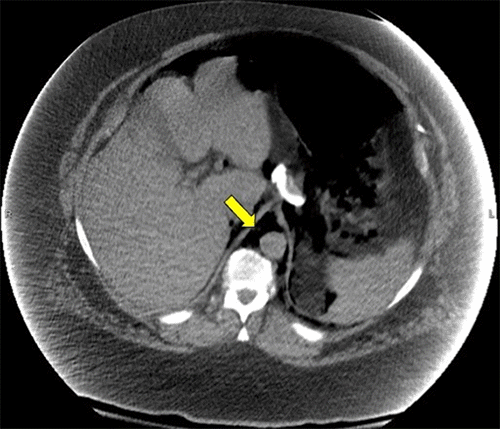

Figure 1. Noncontrast Computed Tomography of the Chest and Abdomen. Published with Permission

A) Chest CT depicting air in pneumomediastinum and B) abdomen CT depicting air in retroperitoneum—yellow arrows show air in both images.

B) Abdomen CT depicting air in retroperitoneum—yellow arrows show air

On the secondary survey, he was found to have marked subcutaneous emphysema of the neck. The abdominal exam was benign, though the authors acknowledge that pain may not have been elicited on exam due to the patient's body habitus. There was an obvious deformity of the right lower extremity, confirmed by an X ray as a right subtrochanteric femur fracture. Noncontrast computed tomography images from the outside hospital demonstrated pneumomediastinum with subcutaneous emphysema, pneumoretroperitoneum, and moderate pneumoperitoneum with air infiltrating throughout the nondependent portions of the abdomen and mesentery.